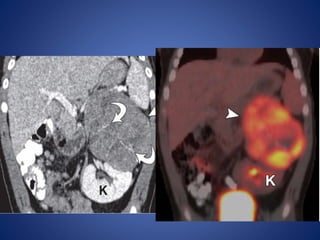

MR imaging demonstratesthe mass as iso- to slightly hypointense on T1WI and hyperintense on T2WI relative to the liver. Functioning ACNs frequently show uniform signal loss at chemical shift imaging due to intracytoplasmic lipid. (FDG) PET/CT is sensitive for the detection of ACNs due to their metabolic activity. The main role of FDG PET in the evaluation of patients with ACN is detection of distant metastases.

• #39 Coronal reformatted CT image shows the left adrenal mass (arrowhead) with enhancing bands in a radiating or stellate arrangement (arrows). Coronal fused positron emission tomographic (PET)/CT image shows increased metabolism in the tumor (arrowhead)